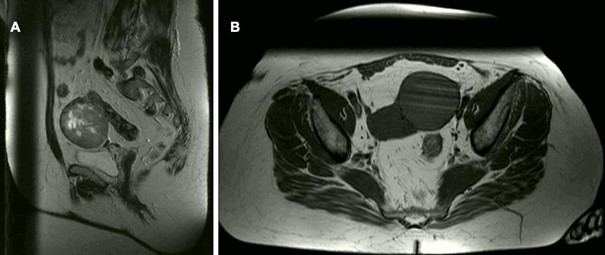

The second case pertains to a 54-year-old obese woman with a history of hypertension and two pregnancies, who presented at our clinic with an initially unclarified, asymptomatic, sonographic suspicious cystic mass measuring 6.6 x 6.4 cm in the left lower abdomen. The patient was referred to our center following a diagnostic laparoscopy at another clinic, which was prematurely terminated due to significant adhesions between the mass and the left pelvic wall, likely attributed to prior surgeries including emergency cesarean section and conventional appendectomy, rendering the findings challenging to interpret. Preoperative tumor markers (CEA, CA 125 and HE 4) were within normal limits. The preoperative MRI showed a cystic lesion at the right pelvic wall measuring approximately 3.1 cm. The differential diagnosis included ovarian tumor or cystic lymph node and there were no evidence of suspicious tumor changes. Τhe patient underwent primary laparoscopic intervention. Intraoperative assessment revealed a 7 cm mass in the left lower abdominal wall with evident vascularization, adhering to the left uterus, pelvic wall, and sigmoid colon, suggestive of probable uterine origin. Initially suspected as a uterine leiomyoma, an unsuccessful attempt at laparoscopic excision was made due to profuse bleeding and concerning findings, necessitating conversion to conventional laparotomy. Despite extensive adhesiolysis, the suspicious mass remained unresectable. Rapid pathological evaluation revealed atypical cells, warranting consideration of malignancy, prompting the decision to proceed with total hysterectomy and bilateral adnexectomy. The patient was discharged without complications on the fifth postoperative day.

Figure 3: Radiologic findings in the 2nd case. Cystic lesion at the right pelvic wall measuring approximately 3.1 cm, differential diagnosis includes ovarian tumor or cystic lymph node. Follow-up recommended. Otherwise, no evidence of suspicious tumor changes.

Figure 4: Histopathologic findings in the 2nd case A Overview with numerous large PEComa cells displaying clear cytoplasm; HE staining, magnification x20. B Nests of PEComa cells within a fibroblast-rich and hyaline stroma; HE staining, magnification x100. C As in this case, PEComa cells typically show diffuse and strong positivity for anti-HMB45; magnification x100.